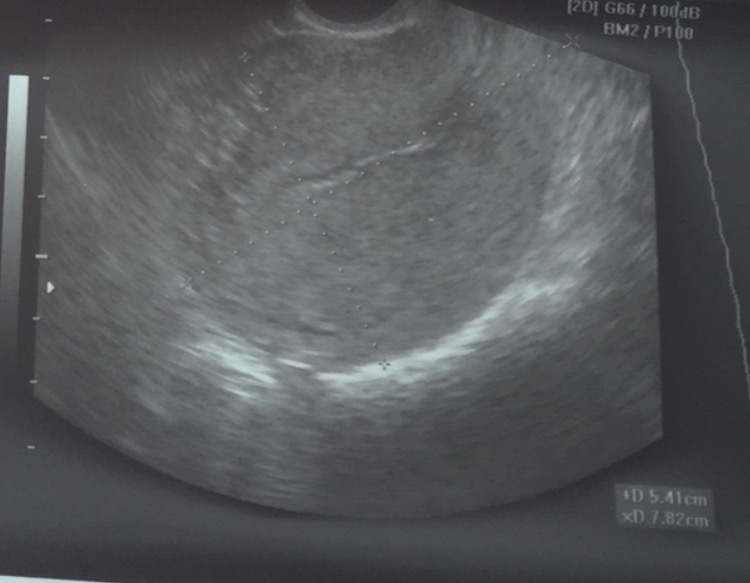

An diesem und folgenden Tag ging es mir bis abends erstaunlich gut kaum Blutungen keine Schmerzen. Nicht nur unmittelbar nach dem Eingriff sondern noch etwa eine Woche lang. Andere Methoden wie eine Ultraschall-Untersuchung oder ein Abstrich geben hierüber oft nur begrenzt Auskunft.